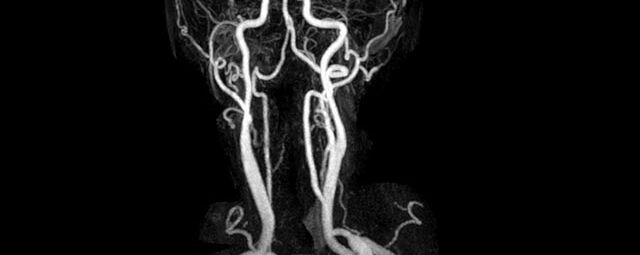

Halsgefäße

• intrakranielle Gefäße (Abklärung Verschluss, Stenose, Aneurysma)

• Halsgefäße zur Therapieplanung (z.B. Stent, Operation)

MR-Angiografie (MRA)

Angiographie ohne Kontrastmittel

• MR-Angiografie ohne Kontrastmittel

• Time of Flight (TOF)-Angiographie

• Phasenkontrastangiographie (PCA). Geeignet zur Quantifizierung Stenose-/Insuffizienzgrad z.B. bei Herzklappen, falls echokardiographisch die Untersuchungsbedingungen eingeschränkt sind.

Je nach Fragestellung und Körperregion Gefäßdarstellung ohne Kontrastmittel bei Kontrastmittelunverträglichkeit oder terminaler Niereninsuffizienz möglich.

Ganzkörper Angiographie mit Kontrastmittel

• MR-Angiographie mit Kontrastmittel

• Erfassung arterieller und venöser Gefäße/Bypässe aller Körperregionen mit 3D-Rekonstruktion

• je nach klinischer Fragestellung zeitaufgelöste MR-Angiographie (4D-MRA) z.B. bei Frage arteriovenöse Fistel/ Shunt oder Darstellung Unterschenkelarterien vor geplanter Bypassoperation.